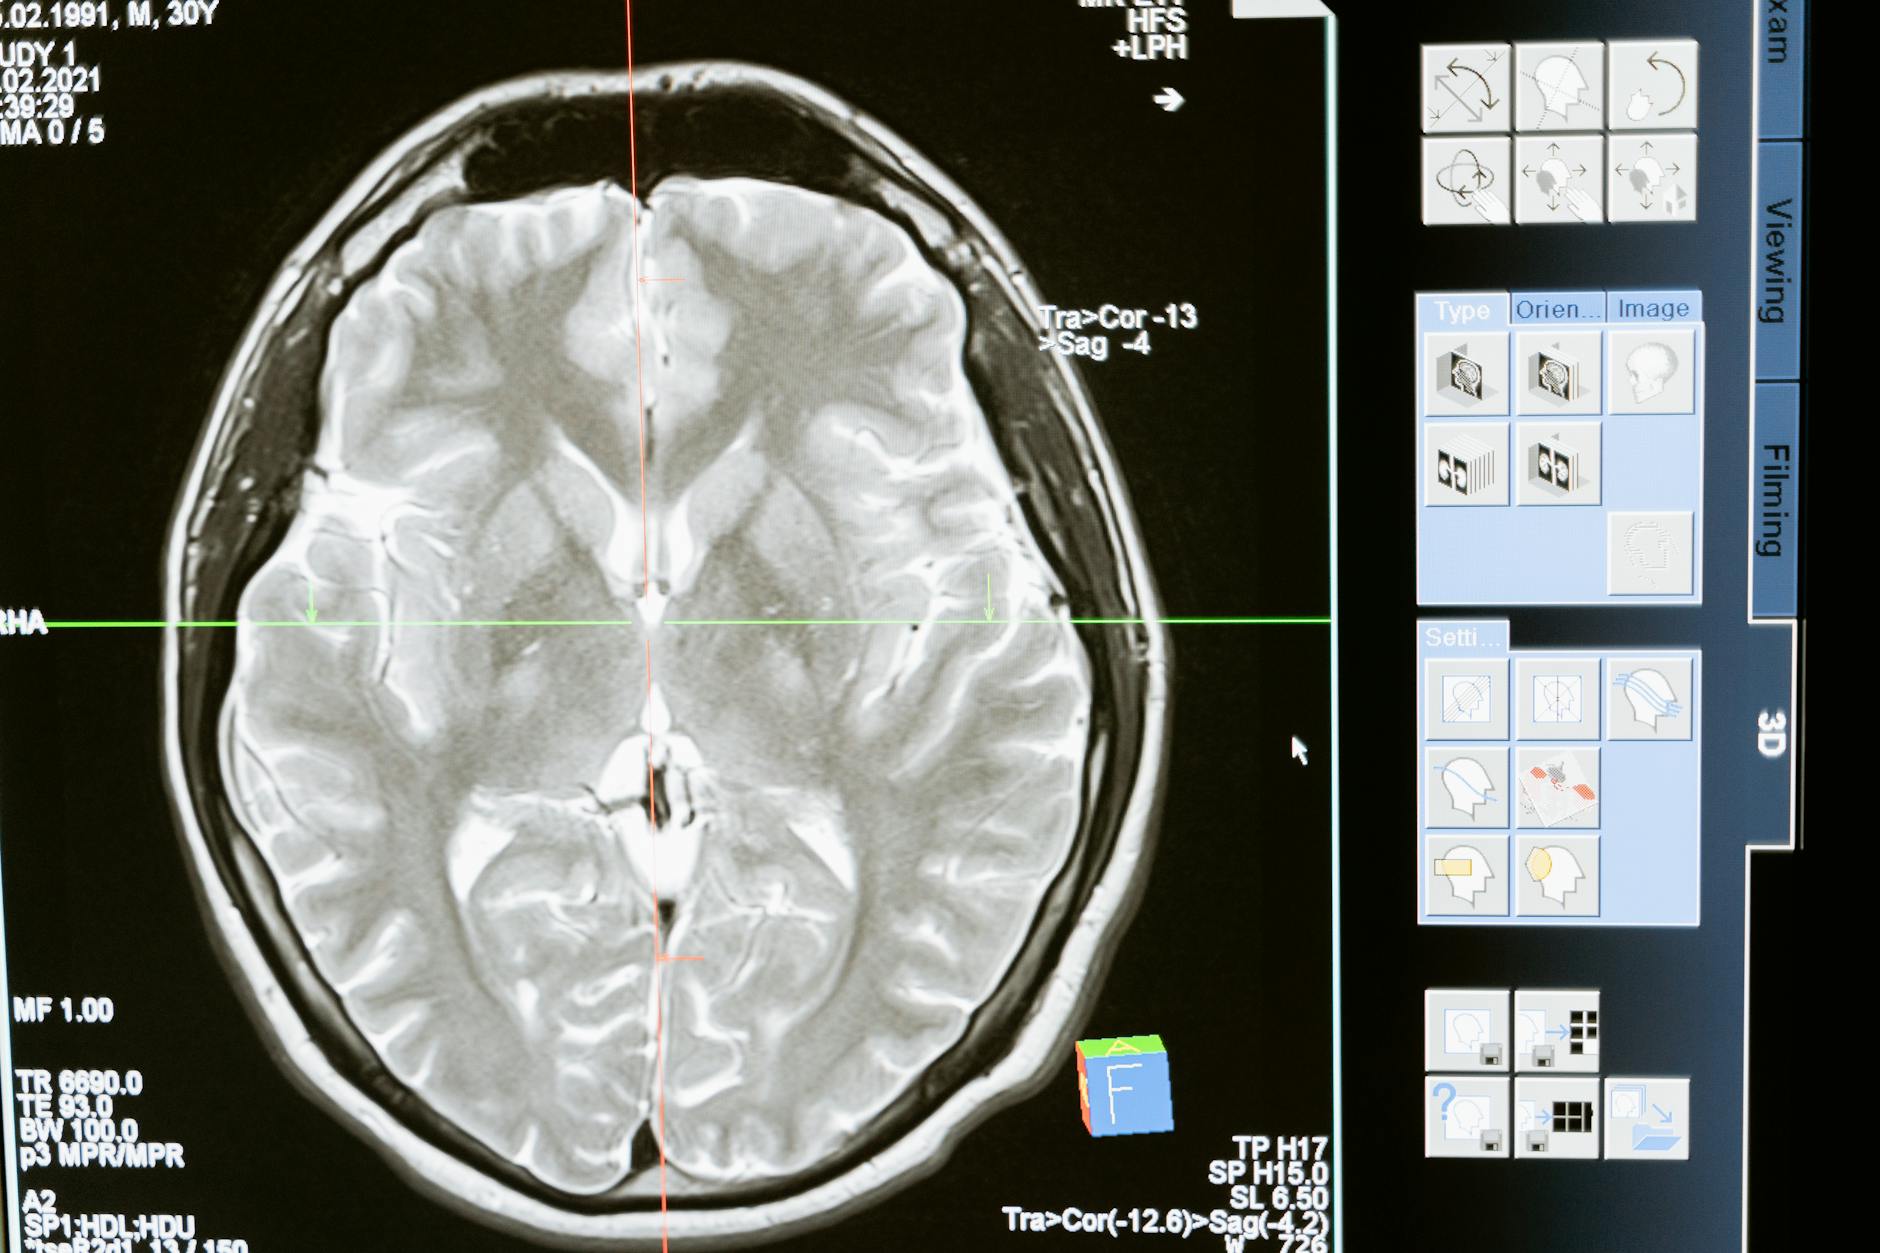

Editorial image for Brain scans shed light on how short videos impair memory and alter neural pathways

Brain scans shed light on how short videos impair memory and alter neural pathways

Neuroimaging studies demonstrate that consumption of short-form videos (typical of social media platforms) correlates with measurable changes in brain connectivity patterns, particularly in regions associated with memory consolidation and attention regulation. The research suggests these brief, rapidly-changing visual stimuli may interfere with the brain’s natural memory encoding processes and alter default mode network activity. While the mechanisms remain under investigation, the findings align with broader neuroscience research on how fragmented attention affects cognitive function.